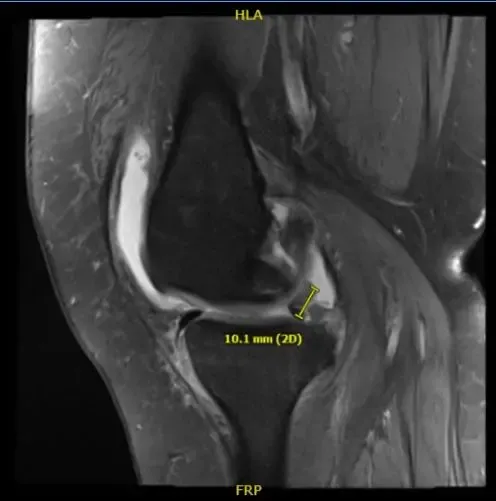

Impresión del resultado de la resonancia magnética es la siguiente: edema de médula ósea en la parte periférica anterior de la meseta tibial medial con ligera aplanamiento e irregularidad de la superficie articular; hay una impactación subcondral de bajo grado o fractura por estrés en cicatrización.

Desgarro complejo del cuerno posterior del menisco medial, incluyendo un colgajo meniscal desplazado que adentra en la raíz posterior y mide 1 cm de longitud. Artrosis patelofemoral severa. Artrosis femorotibial moderada. Derrame articular moderado.

Resonancia magnética de la rodilla derecha